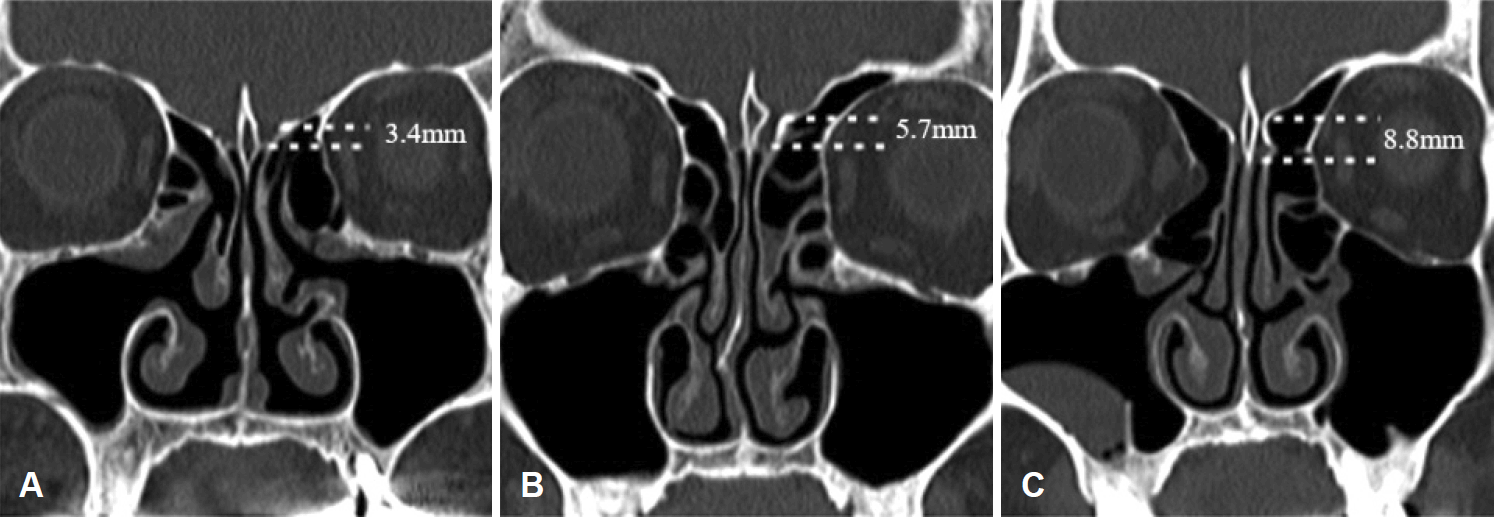

We investigated superior turbinate pneumatization (STP), middle turbinate pneumatization (MTP), agger nasi cell (ANC), infraorbital cell (IOC), optic nerve (ON) type, and vidian nerve (VN) type. We categorized ON canals into four types using the classification system by Itagi, et al. [7] (Fig. 2). Type I canal is superolateral to the SS and does not indent on the sinus wall, as seen on the coronal CT planes. Type II canal is indented on the SS contour and the indented portion is less than 50% of the nerve circumference. Type III canal traverses through the SS and coronal sections showing more than 50% projection of ON circumference into the SS. Type IV is a canal adjacent to the SS and posterior ethmoid sinuses/Onodi cell. Configurations of the VN were classified into three types (Fig. 3). Type I is considered when the VN canal completely protrudes into the SS; type II, when the canal partially protrudes into the SS or into the floor of the SS; and type III, when the canal is completely obscured within the sphenoid corpus [8].

The LLL was measured as the distance between the fovea ethmoidalis and the horizontal cribriform plate in the olfactory fossa, as observed on the coronal plane in which the crista galli was well observed (Fig. 4) [3]. Two otolaryngologists analyzed each case, and on disagreement, a unified opinion was considered after referring to a third otolaryngologist.